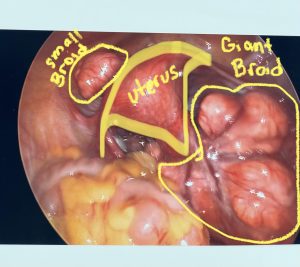

Which Size Of Fibroid Is Dangerous